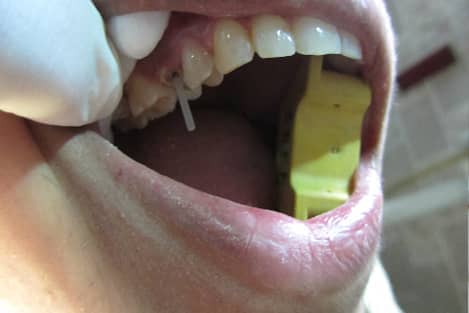

Dental Dam Isolation